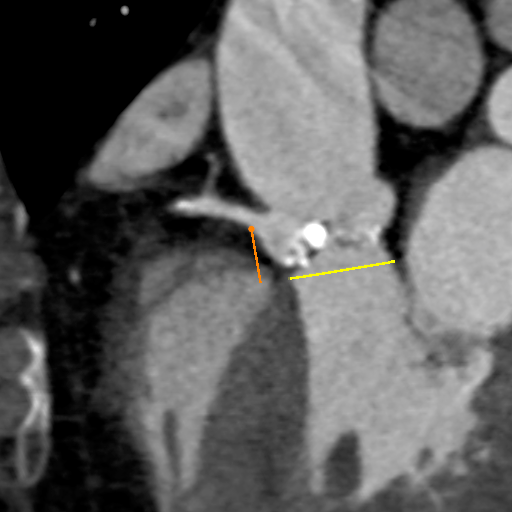

主动脉CT

主动脉瓣环平均直径:22.1mm;

左室流出道平均直径:23.7;

左冠脉开口:12.3mm;

右冠脉开口高度:11.2mm。

术前讨论:患者为三叶瓣主狭,左右冠瓣叶长,开口低,瓦氏窦小,左右冠高风险。

袁义强院长总结了该病例特点:三叶瓣,左右冠均高风险,解剖适合TAVR,年龄73岁,存在明确TAVR手术适应症。选择右股动脉入路,根据CT测量分析选择瓣膜大小,窦部情况可,瓣环平均直径22.1mm,计划22号球囊预扩,评估冠脉风险,选择植入24mm瓣膜。